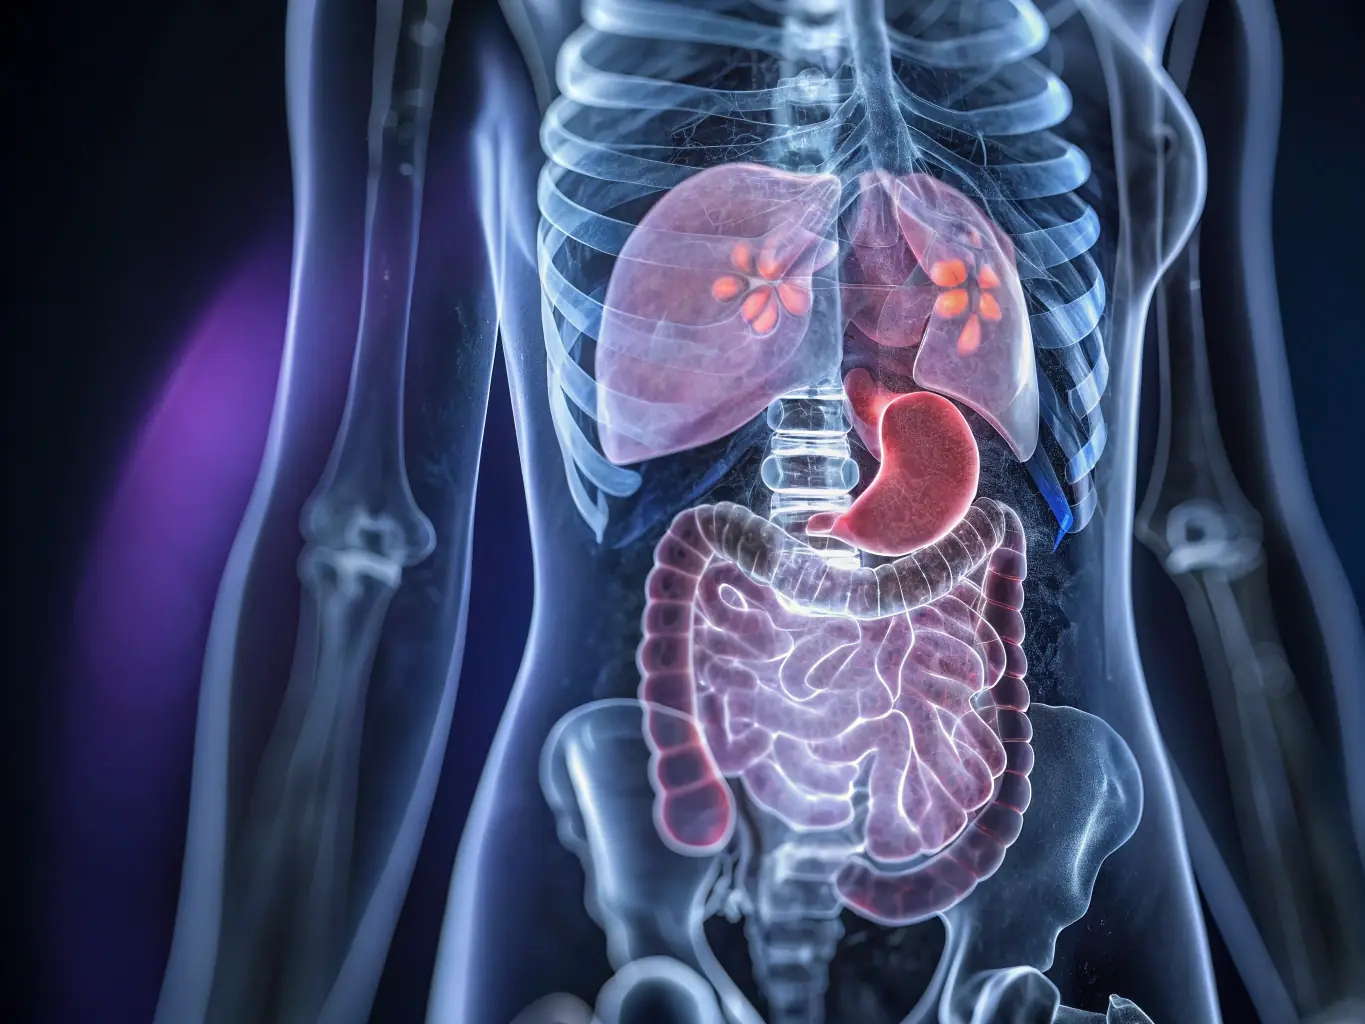

A detailed MRI image of the abdomen, clearly showing internal organs such as the liver, kidneys, and pancreas, taken in a diagnostic imaging center.

Abdominal and Pelvic Imaging

Our MRI scans of the abdomen and pelvis help diagnose conditions affecting the liver, kidneys, bladder, and reproductive organs. We provide thorough and reliable imaging services.